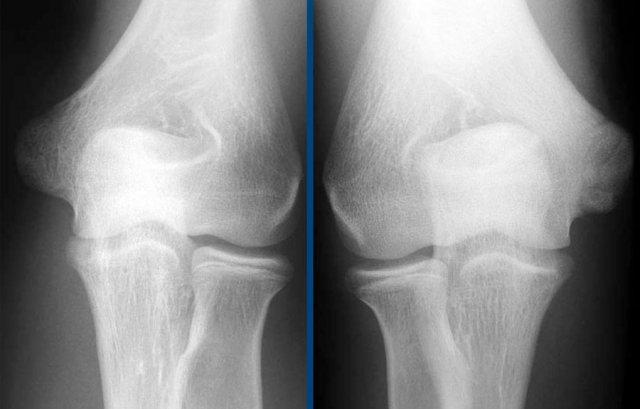

Pseudodefect of the capitellum

Đây là một phát hiện mà bạn thường thấy trên các hình ảnh mặt phẳng coronal.

Trông có vẻ giống như một tổn thương sụn xương, nhưng nếu bạn nhìn vào hình ảnh mặt phẳng sagittal, bạn sẽ nhận thấy rằng hình ảnh mặt phẳng coronal đi qua phần không có khớp phía sau của chỏm con.

Vì vậy, khi khuỷu tay duỗi hoàn toàn, một phần của chỏm quay thực sự nằm phía sau bề mặt sụn khớp của chỏm con.

Trên hình ảnh mặt phẳng coronal, chúng ta sẽ quan sát thấy chỏm quay được bao phủ bởi sụn và đối diện với nó là phần không được bao phủ bởi sụn của chỏm con, phần này thường có phần không đều.